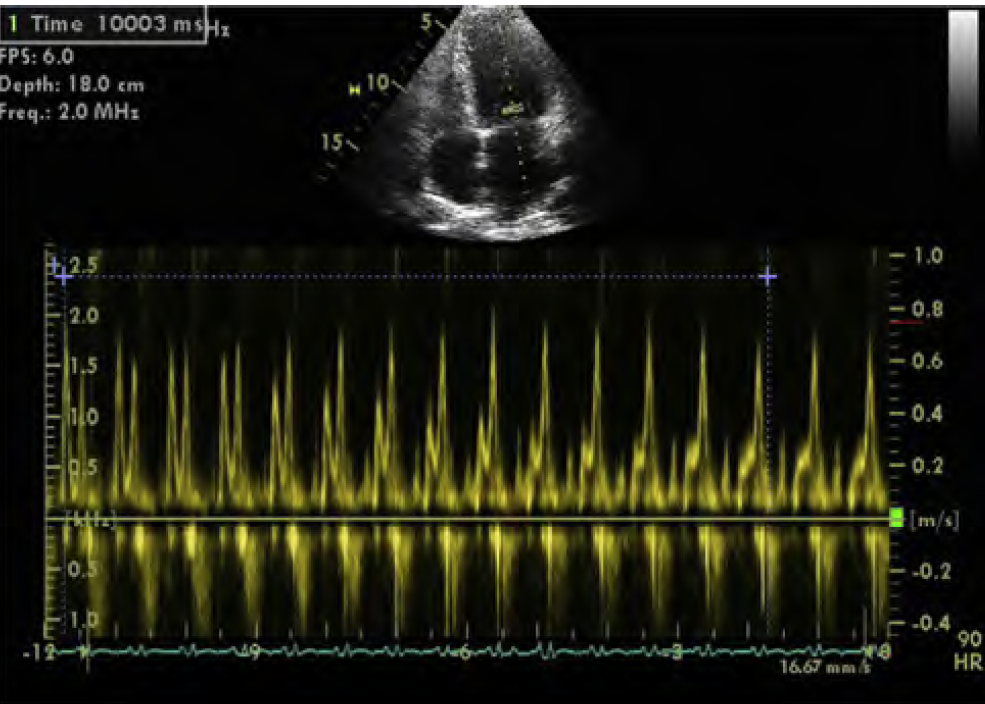

***Continuous recording of mitral inflow during standardized Valsalva maneuever for 10s –> decrease in E/A ratio with straining, which is consistent with elevated LV filling pressures